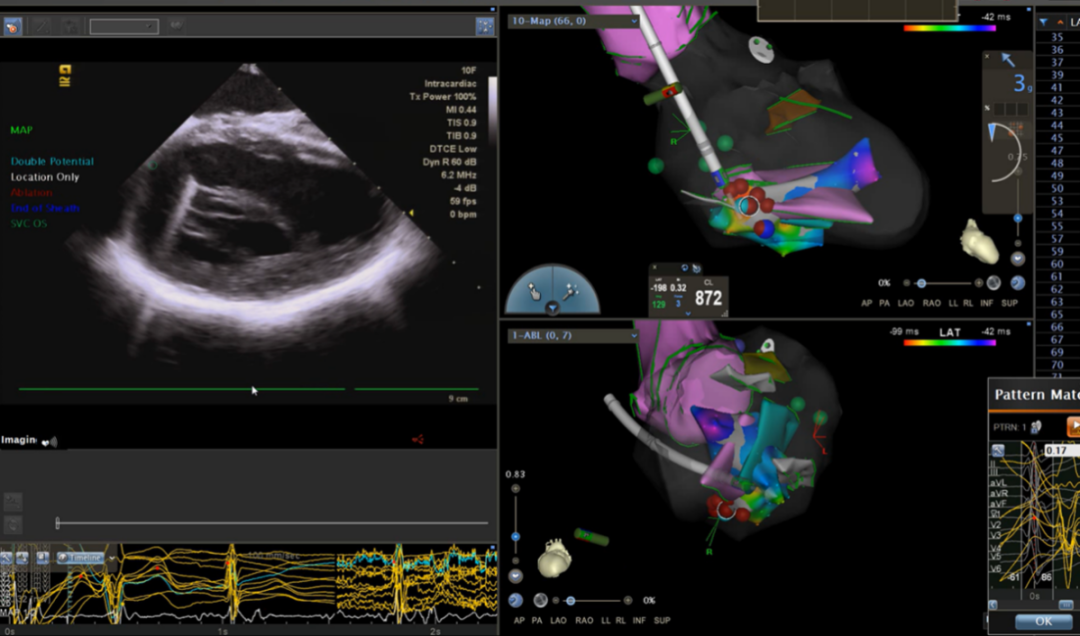

31岁男性患者,因心悸半年、胸闷痛3天于2022年5月22日入院,曾在山东某院就诊行动态心电图检查提示频发室早、室速,于是来我院寻求治疗。动态心电图提示有两种主要形态的室早,一种位于右室流出道,该形态有室速发作,另一种位于三尖瓣希氏束旁。患者上台后室早数量较少,行常规的激动标测作用有限,根据术前对室早的精准定位,结合起搏标测把第一种形态室早消融成功。随后标测第二种形态室早,位于希氏束上方,常规贴靠非常困难,术者采用少用的“α”弯稳定贴靠希氏束上方,最终消融成功。

希氏束旁室早消融靶点

希氏束旁室早“α”弯消融